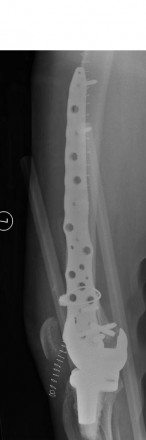

Case 2

This 73 years old female patient fell in bathroom 4 weeks after routine TKR. She sustained Lewis & Rorabeck Type 2 periprosthetic fracture of TKR.

The fracture was reduced and fixed with Zimmer cable ready cerclage cable and 9 holes distal femur NCB periprosthetic plate.

Provided by Mr Aaron Ng FRCS (Tr & Orth), Pinderfields General Hospital, Wakefield, UK.